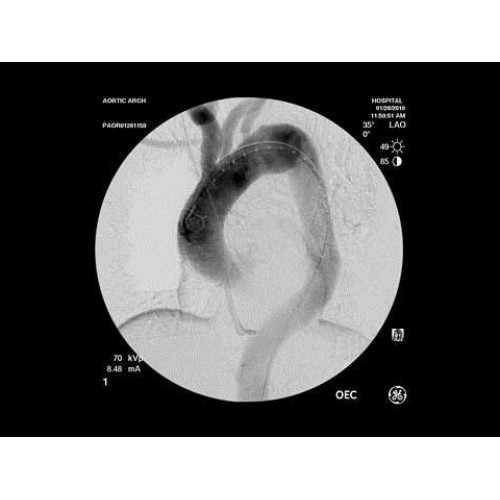

• Кардиохирургические вмешательства и ангиопластика

• Сосудистая хирургия

В ведущих медицинских центрах GE OEC 9900 Elite успешно применяется для проведения сложных кардиологических, нейрохирургических и ортопедических вмешательств. Система доказала свою эффективность при выполнении стентирования коронарных артерий, эмболизации сосудов головного мозга и вертебропластики. Многие учреждения отмечают повышение качества операций после внедрения этого оборудования.